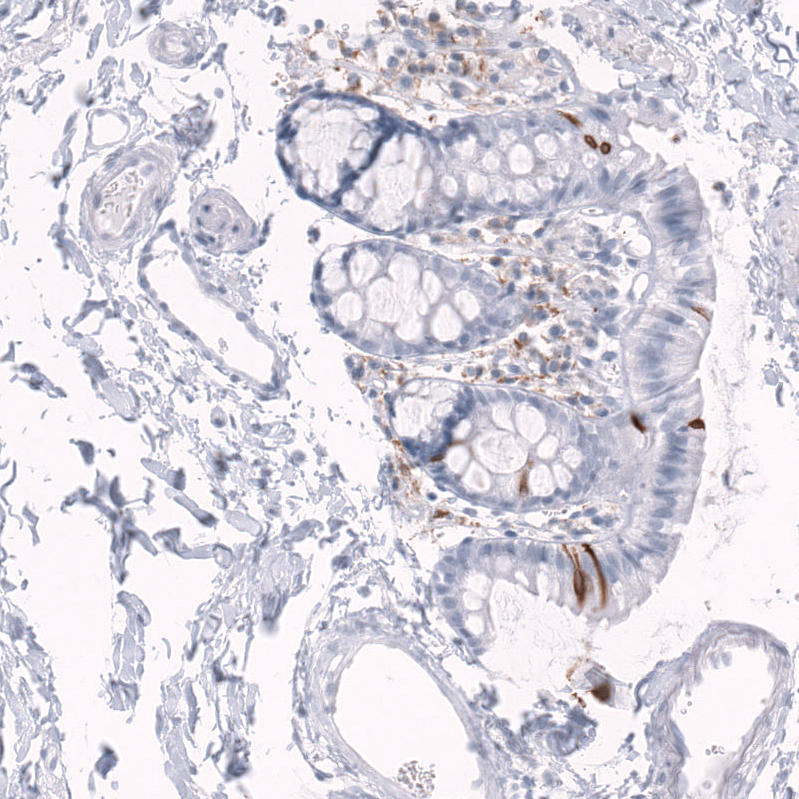

Immunohistochemical staining of human rectum shows strong membranous positivity in subset of glandular cells and cytoplasmic-membranous positivity in lymphoid cells.